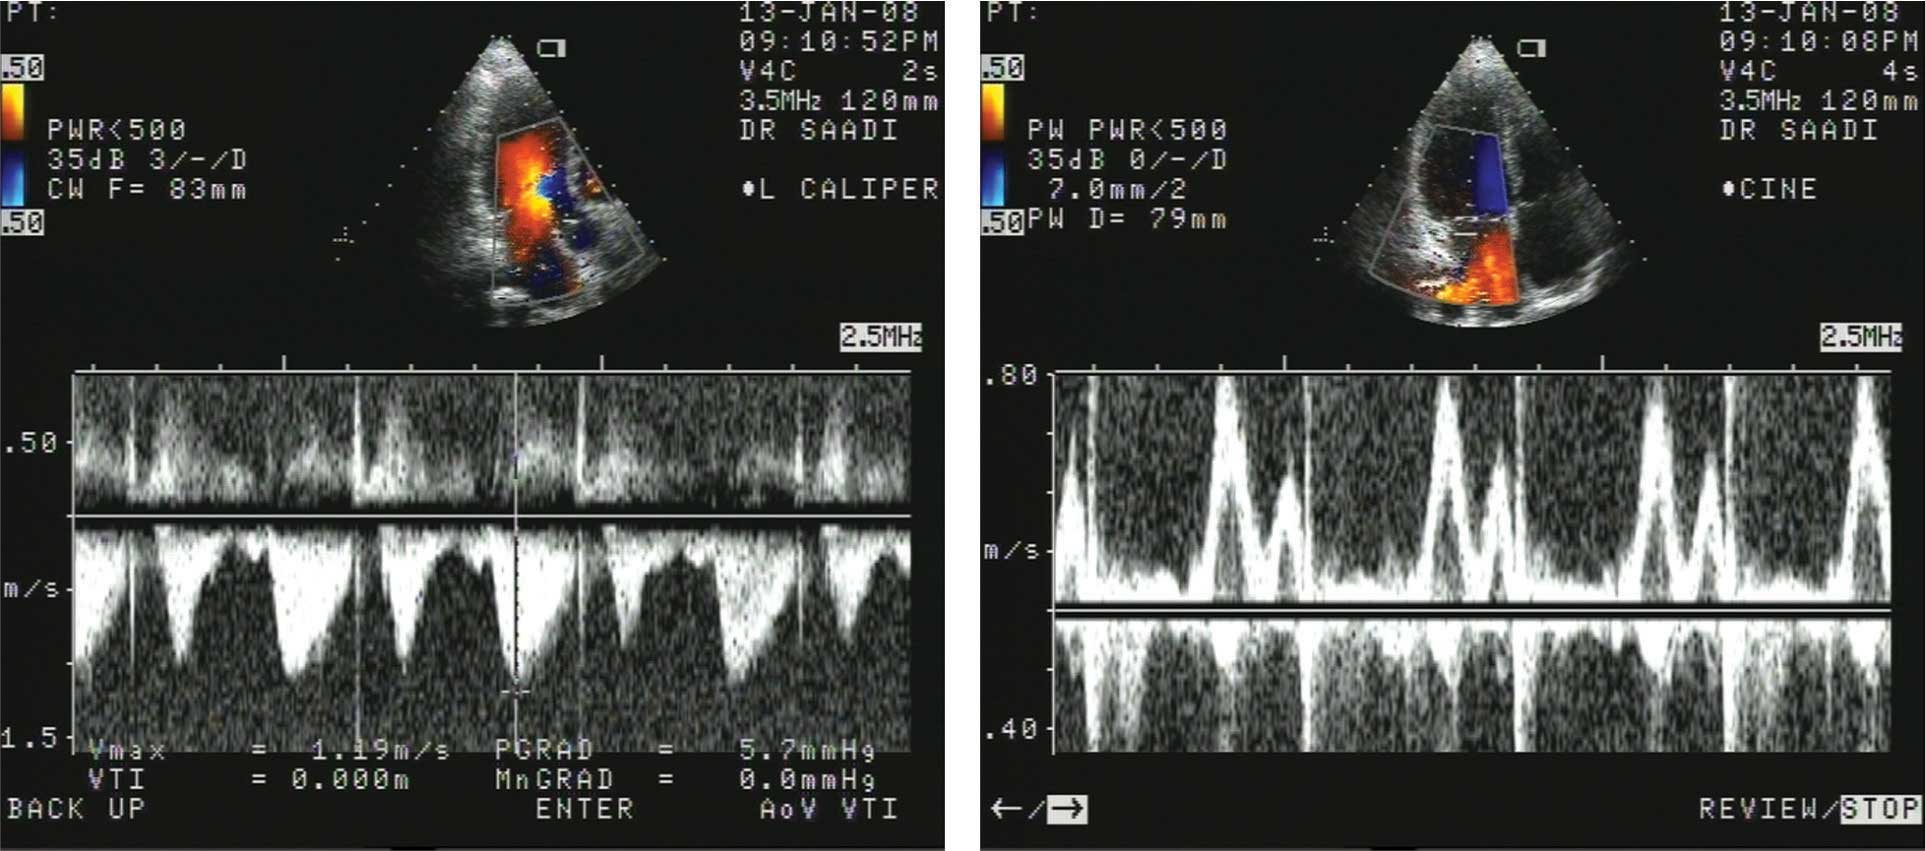

أ- الدوبلر النبضي (الشكل6).

ب- الدوبلر المستمر (الشكل6).

الشكل (6) صورتان بالدوبلر: الأولى على اليمين للجريان عبر الصمام التاجي بالدوبلر النبضي، والثانية على اليسار للجريان عبر الصمام التاجي بالدوبلر المستمر. |